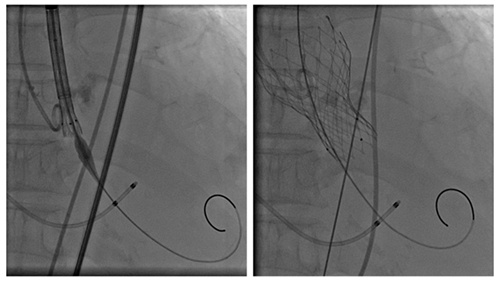

狭路相逢勇者胜!6月29日下午,黄阿姨在东院复合手术室进行手术。全麻后,黄阿姨出现了明显的循环波动,王萍主任医师、王洪乾主治医师、张祎医师组成的麻醉团队精准预判并及时调整血管活性药物,使黄阿姨血流动力学迅速趋于平稳。心内科王勇主任医师带领李少华副主任医师、张明伟副主任医师组成的TAVR手术团队快速完成了临时起搏器置入及冠脉造影;心外科李勇主任医师、孙翔飞主治医师游离右侧腋动脉、股静脉插管建立体外循环,焦齐副主任医师负责转机维持术中循环稳定;在没有术前主动脉CTA做参考情况下,超声医学科李巧副主任医师术中实时超声引导,心内科TAVR手术团队选择右股动脉入路,结合超声与主动脉根部造影,明确了最佳体位,完成导丝跨瓣、球囊预扩以及最终的瓣膜释放。整个手术过程一气呵成,体外循环顺利停机,无明显并发症,最担心的左心室血栓也“安分守己”,见证着手术的成功。